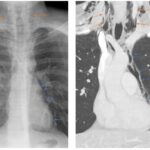

Dentro de los métodos diagnósticos, el neumomediastino se puede diagnosticar mediante radiografías o tomografía computada, donde se va a visualizar la presencia de aire (radiolucidez o hipodensidad lineales) rodeando las estructuras mediastinales. Un signo de muy alta especificidad es el llamado “signo del anillo alrededor de la arteria”, donde se visualiza una imagen radiolúcida o hipodensa en forma de anillo rodeando la arteria pulmonar, principalmente del lado derecho. Este signo ayuda a diferenciar esta entidad del neumopericardio, que puede verse similar en imágenes.

Among the diagnostic methods, pneumomediastinum can be diagnosed using X-rays or computed tomography scans, where the presence of air (linear radiolucency or hypodensity) surrounding the mediastinal structures will be visualized. A highly specific sign is the so-called “ring sign around the artery”, where a radiolucent or hypodense ring-shaped image is visualized surrounding the pulmonary artery, primarily on the right side. This sign helps differentiate this condition from pneumopericardium, which can appear similar on imaging.